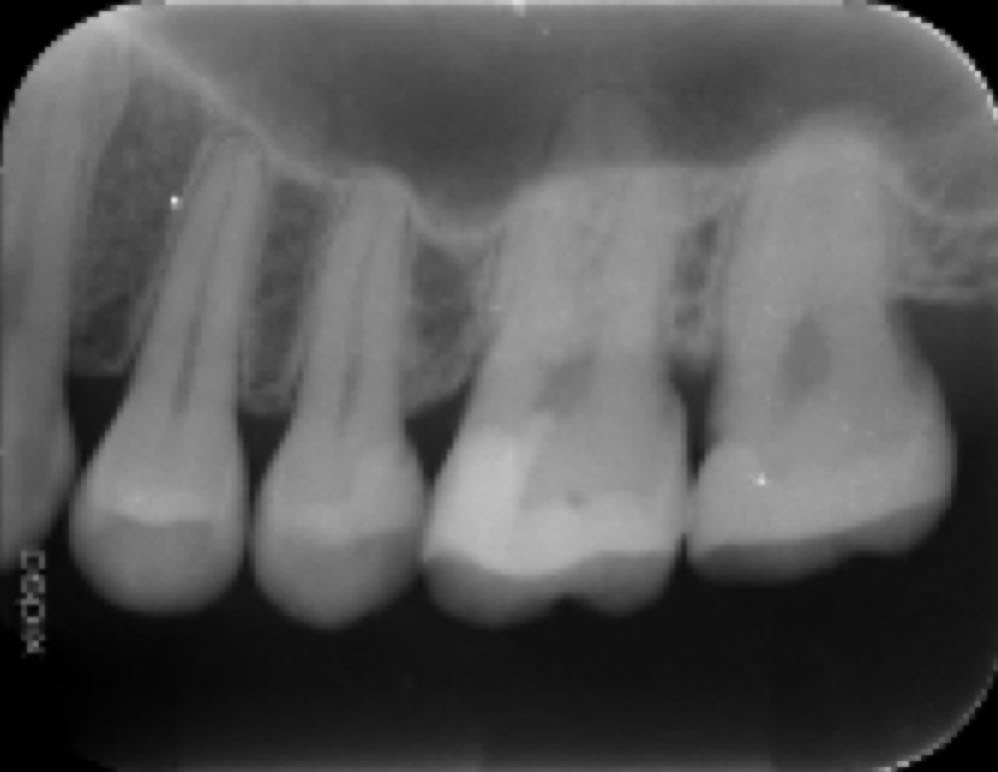

術前

術後

初回の根管治療の成功率は比較的高く細菌感染レベルが低い場合は適切に治療すればGP(一般歯科医)でも成功する可能性は高いと思われます。ただし、術者の歯内療法におけるトレーニングの習熟度により成功率にばらつきが出ます。

日本全国で行われている一般的な根管治療の成功率は50%以下と推測されます。(日歯内療誌 32(1): 1~10, 2011より私的解釈)